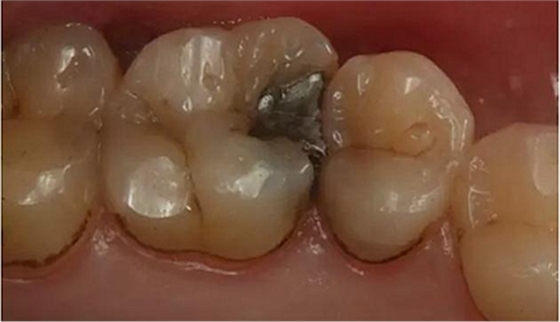

病例一 女性,20歲,大學(xué)生,要求補牙,檢查口內(nèi)可見A6大面積缺損,近中牙齦息肉,拍X片,根管充填物略差,但根周未見明顯陰影,口內(nèi)檢查無叩痛。建議患者冠延長手術(shù)+高嵌體修復(fù)。

患牙遠(yuǎn)中邊緣嵴完整,強度沒有降低,故擬保留遠(yuǎn)中邊緣嵴,高嵌體修復(fù)。首先去除腐質(zhì)及原墊底材料,流體樹脂+3M Z350XT樹脂墊底。局麻下行冠延長手術(shù)。在此需要提及個人的一個觀點。冠延長手術(shù)原則上要求3-6個月以上才能永久修復(fù)。但是個人喜歡后牙肩臺建立在齦上,所以修復(fù)后的修復(fù)體邊緣位于牙齦上方1mm,對牙周的愈合影響較小(如果為齦下邊緣則要慎重),故該患者術(shù)中按照齦上邊緣的設(shè)計進行冠延長手術(shù)。以下為術(shù)中: